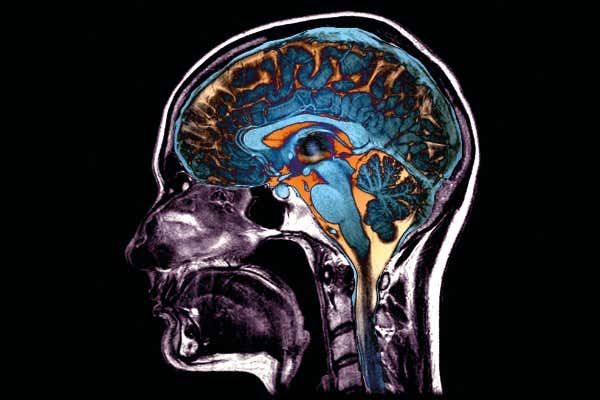

Mnogi ljudi koji su preboljeli covid-19 imaju značajno lošije rezultate na testovima inteligencije nego što bi se očekivalo, pokazala je velika studija nedavno objavljena u Lancetovom časopisu EClinicalMedicine, prenosi Index.hr.

Znanstvenici s Imperial Collegea London koji se bave istraživanjem mozga u studiji su koristili rezultate Velikog britanskog testa inteligencije, koji je pokrenut još 2019.

Nakon što su uzeli u obzir i isključili utjecaje varijabli kao što su dob, spol, obrazovanje, prihodi, rasna i etnička pripadnost, povijest bolesti, depresija, umor, raniji mentalni problemi i zanimanje, znanstvenici su otkrili da su oni koji su se zarazili virusom imali značajno lošije rezultate od očekivanih u odgovarajućoj demografskoj skupini.

Bolesnici koji su završili na respiratorima imali su najveći deficit, jednak padu IQ-a za sedam bodova, no pad je zabilježen čak i kod osoba koje su preboljele blagi oblik bolesti.

“Deficiti su bili značajni kod hospitaliziranih osoba (N = 192), ali i kod nehospitaliziranih koje su imale biološku potvrdu infekcije covidom-19 (N = 326). Analiza markera premorbidne inteligencije nije pokazala da su ove razlike postojale prije infekcije. Finija detaljna analiza izvedbe kroz podtestove podržala je hipotezu da covid-19 ima utjecaj na više domena ljudske spoznaje”, tumače autori.

“Pad je bio najizraženiji u područjima u kojima se koriste kognitivne funkcije, poput zaključivanja, rješavanja problema, prostornog planiranja i otkrivanja ciljeva.” Ovi rezultati u skladu su s izvješćima o dugom covidu, u kojima se uobičajeno spominju moždana izmaglica, problemi s koncentracijom i poteškoće u pronalaženju točnih riječi”, dodali su znanstvenici.